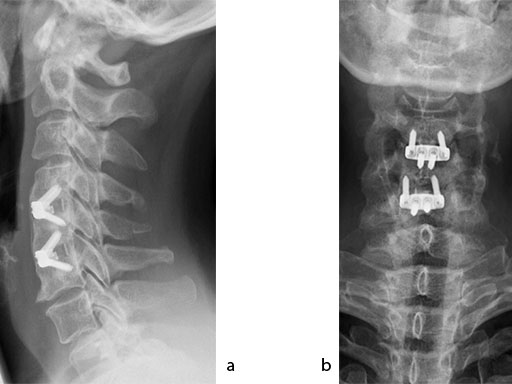

A 51-year-old woman was affected by cervical radiculo-myelopathy due to spinal and neuroforaminal stenosis. The preoperative CT scans are shown at Fig 4 and MRI at Fig 5.

The patient was treated by anterior cervical decompression and fusion (ACDF) with ZERO-P filled with ChronOS. No autologous bone graft was used. Postoperative images are shown (Fig 69).